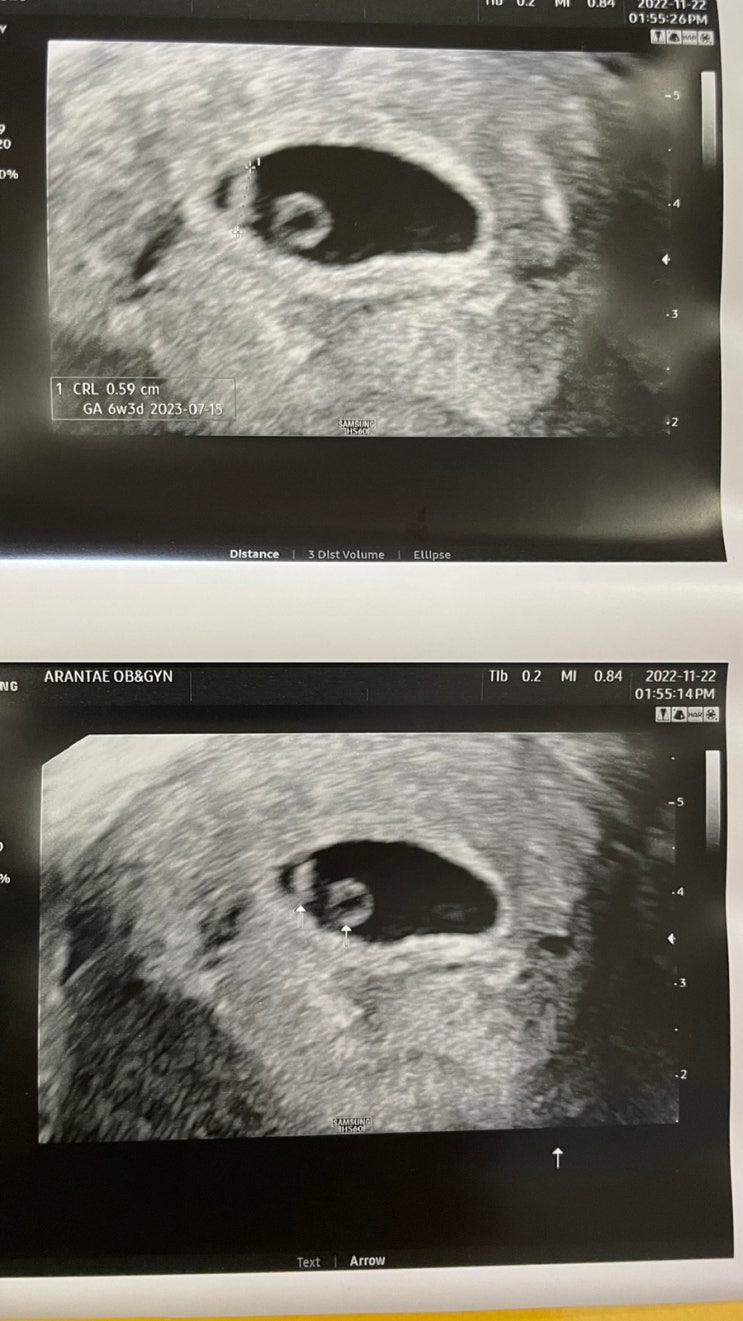

임신 5-6주차 증상, 심장소리, 입덧시작, 출산 예정일 수정

이 블로그를 쓰고있는 지금. 6주 4일차, 입덧인지 쳇기인지 모르겠지만 속이 매우 불편하여 끝없이 일부러 ...